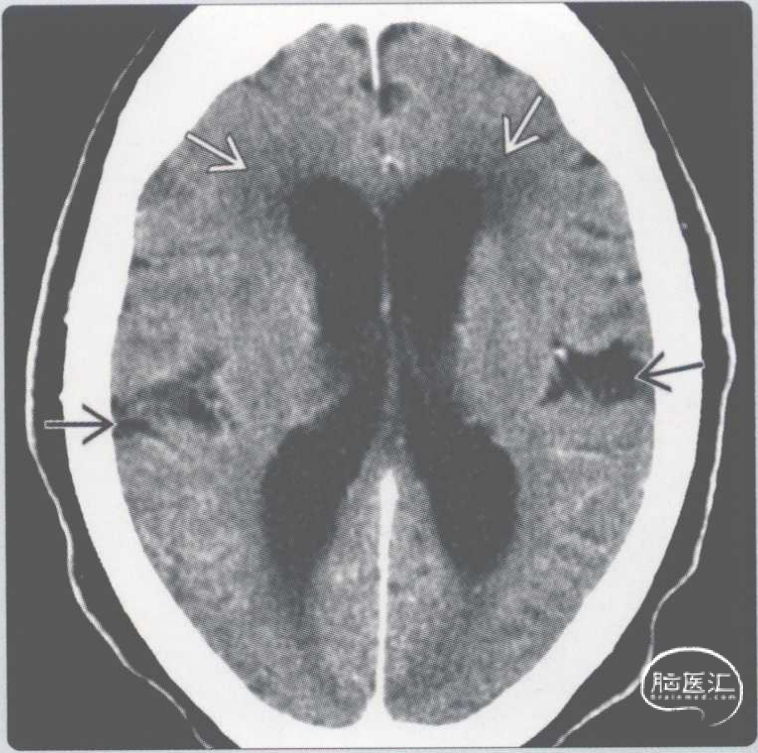

【影像时间·273】一位正常压力性脑积水(NPH)患者